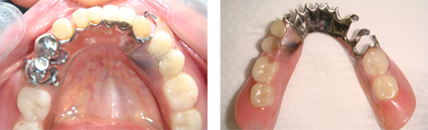

拆下牙橋前

拆下牙橋後